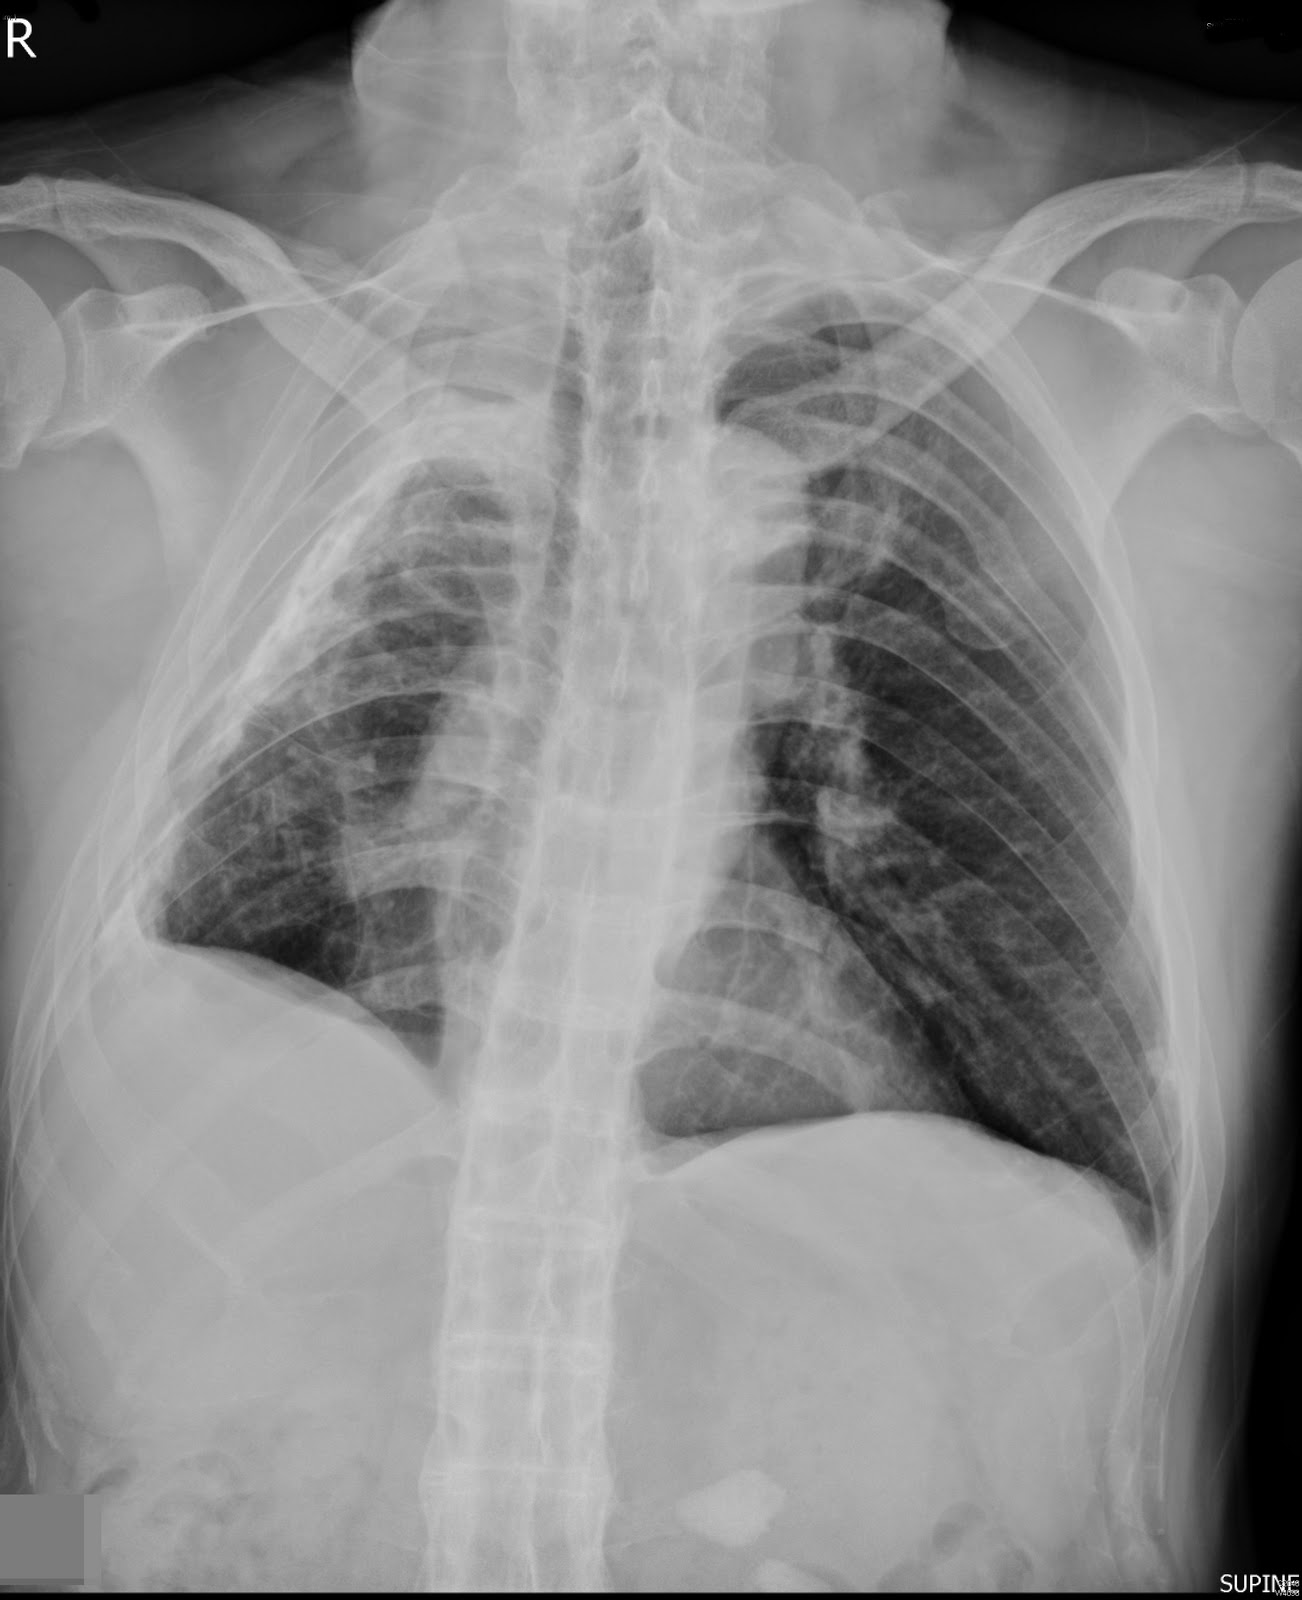

Ankylosing spondylitis (AS) with fibrothorax From pulmmed.blogspot.com

Ann rheum dis (2013) doi:10.1136 published online first, april 26. Ankylosing spondylitis may be noted when apical fibrosis is present; Reactive arthritis is a group of symptoms that includes inflammation of the joints, urethra, and eyes as well as skin lesions. 7/25/2019 ankylosing spondylitis and undifferentiated spondyloarthropathy 1/33ankylosing spondylitis and undifferentiatedspondyloarthropathy author: Ankylosing spondylitis affects the spine and sacroiliac joints.the symptoms start appearing commonly in the second and third decade of life.

Ankylosing spondylitis (as) is a seronegative spondyloarthropathy and a chronic inflammatory disease of the axial skeleton that leads to partial or complete fusion and rigidity of. Ankylosing spondylitis may be noted when apical fibrosis is present; Hla b27 in ankylosing spondylitis: Health topics symptoms and signs supplements medications slideshows images quizzes. Ankylosing spondylitis is a chronic and progressive form of inflammatory arthritis.